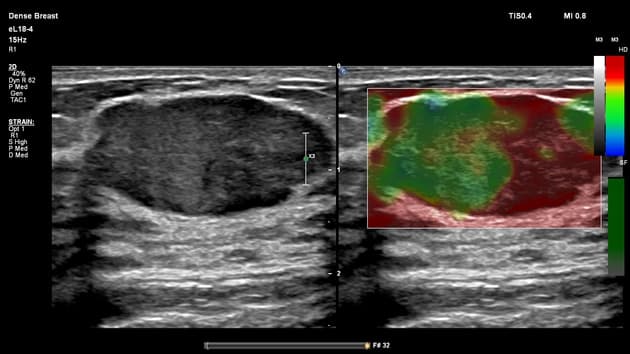

- Có một tổn thương đặc hình bầu dục, ranh giới rõ, giảm âm, kích thước khoảng 30x15 mm ở vùng vú phải ngoại biên. Tổn thương định hướng song song với da.

- Tổn thương thể hiện chủ yếu mô hình khảm (điểm Tsukuba: 2) với các vùng độ cứng hỗn hợp, phù hợp với tổn thương lành tính như adenoma vú (fibroadenoma).

Siêu âm đàn hồi (elastography) có thể cung cấp thêm độ tin cậy chẩn đoán, vì adenoma vú thường thể hiện mô hình khảm đặc trưng, trái ngược với hình ảnh độ cứng đồng đều thường thấy ở các tổn thương ác tính.

- "Siêu âm đàn hồi có thể hỗ trợ phân biệt khối u lành tính và ác tính, với adenoma vú thường cho thấy mô hình độ cứng dạng khảm (điểm Tsukuba 2)."